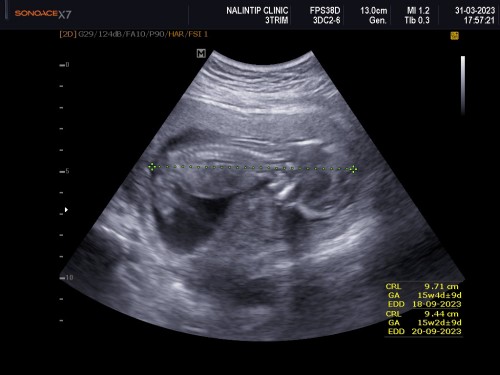

ภาพอัตซาวด์ตอน14/5w

พอดีหมอนัดประจำเดือนดูน้อง น้องนอนอยู่ในท่านี้ถือว่าปกติไหมคะ เราค่อนข้างกังวนมาก แต่คุณหมอก็บอกอยู่ว่าปกติทุกอย่าง แต่น้องนอนคว่ำ มีแม่ๆบ้านไหน ซาวด์ดูน้องแล้วนอนคว่ำหน้าแบบนี้บ้างคะ 😅